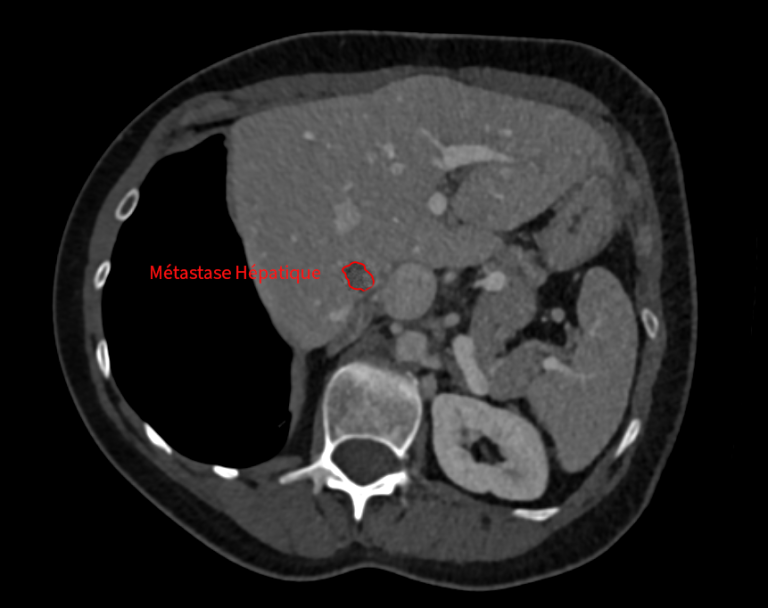

Suivie pour un cancer colorectal métastatique, elle présente une nouvelle récidive avec :

• une métastase hépatique de 1 cm, profonde et difficilement accessible chirurgicalement.

Traitement hépatique par micro-ondes

Dans un second temps, la métastase hépatique est traitée par thermoablation micro-ondes, avec protection des organes voisins grâce à une technique d’hydrodissection.

Images du traitement des organes (poumon et foie) avant, pendant et après le traitement.